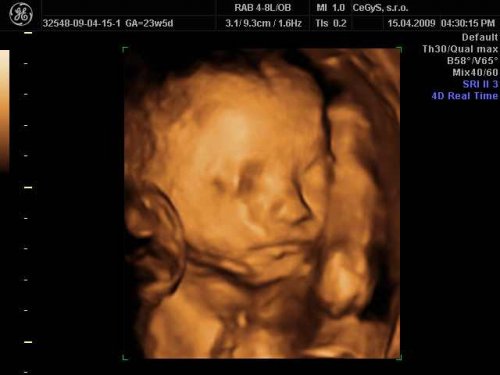

Čakáme bábo